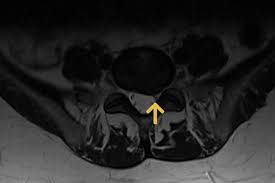

Bei Zysten oder Vernarbungen im Bereich des Gehirns hindeuten. Zur weiteren Differenzierung zwischen den Ursachen der Flecken sind Tests erforderlich die in der Regel durch einen Neurologen durchgeführt werden. Das Rückenmark als Schlüssel zur MS-Diagnostik. MRT der LWS T2 linkes Bild Weiß kann man die Entzündung der Lendenwirbelsäule erkennen da die Bandscheibe durch die Fehlstellung aufgebraucht wurde und nun Knochen auf Knochen reibt und eine Entzündung des Knochens entsteht. Ich habe viele mrt bilder von mir daheim. 7 Wochen ein MRT der HWS mit der Diagnose Foraminastenose bds cervicaler Bandscheibenschaden Z. Ein Computer wandelt diese Signalen in sichtbare Bilder um.